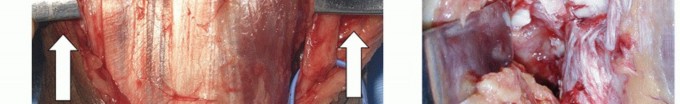

Develop the full-thickness medial and lateral skin flaps (TECH FIG 1B) and define the medial and lateral borders of the triceps (TECH FIG 1C,D).

TECH FIG 1 • A. Skin incision is posteriorly longitudinal, with or without a small diversion to avoid the “point” of the olecranon. B. Raising the skin should aim to maintain the full thickness of the flaps by using the “flat knife” technique. C. The medial and lateral borders of the triceps are defined (arrows). D. This patient had an anconeus epitrochlearis (star) in relation to the ulnar nerve (UN). E. A vessel loop is used to maneuver the nerve without an attached clip. F. The medial fragment of the fracture is removed once all the soft tissues are released from it, and the nerve is gently retracted to ensure tension-free removal.

At the medial border, define and partially neurolyse the ulnar nerve, and mark and handle it with a tied vessel loop (without an attached hemostat because its constant weight may cause inadvertent nerve injury) (TECH FIG 1E).

Remain in the medial gutter to extend the dissection distally to define the medial fracture fragment. Release the flexor-pronator mass and medial collateral ligament from the medial epicondyle and resect this bony fragment (TECH FIG 1F).